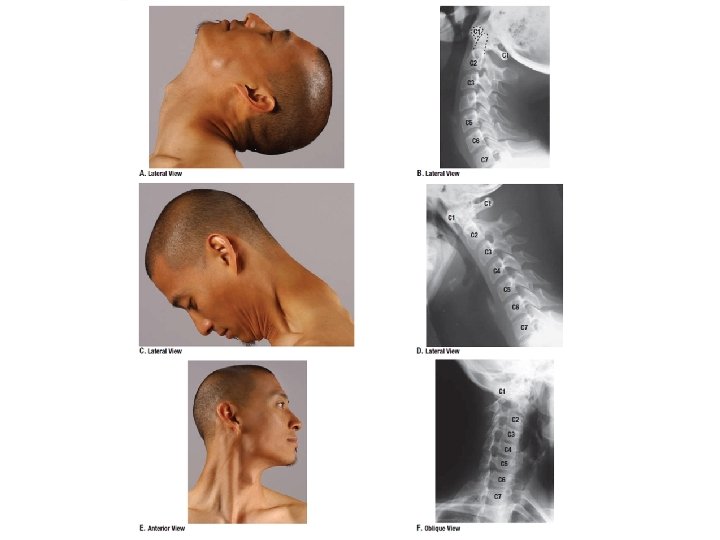

Nyaki gerinc: mozgékony ízületi felszínek: vízszintes állásúak mozgások: lateralis flexio ventralflexio és dorsalflexio (extensio) rotatio articulatio atlanto-occipitalis mozgások : -fej bólintása + hátreszegése (igenlő mozdulat) -> haránt tengely körül -fej ingatása egyik válltól a másikig -> sagittális tengely körül articulatio atlanto-axialis mozgás: fej rotációja („nem” mozdulat) (függőleges tengely körül)

A fej ízületei art. atlanto-occipitalis: art. ellipsoidea sagittalis és haránttengellyel art. atlanto-axialis: art. trochoidea vertikális tengellyel 2+1 tengely Bár a nyaki gerinc egészében is meglehetősen mozgékony, a fej mozgásai nagyobbrészt e két fejízületben valósulnak meg!